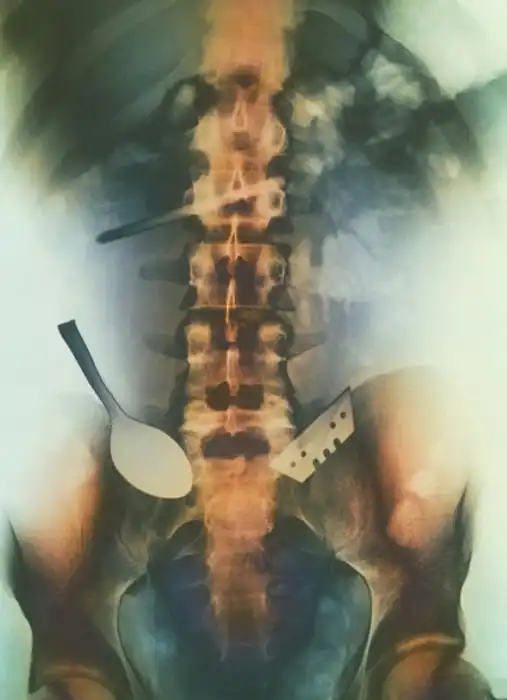

Жуткие рентгеновские снимки

Порой даже не верится, с какими странными и необычными повреждениями в травматологию могут поступить пострадавшие. Всю эпичность профессии врачей травматологии могут с легкостью подтвердить рентгеновские снимки.